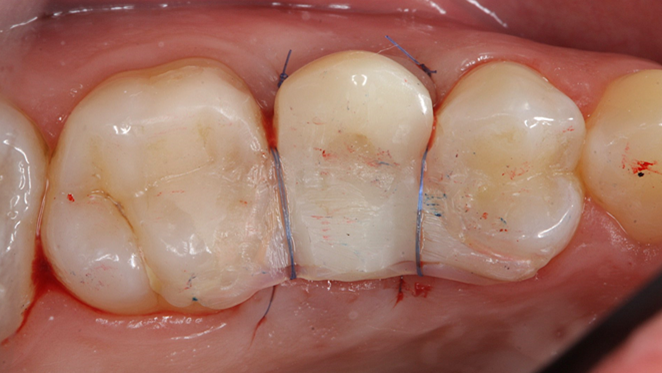

Clinical case: Extraction, immediate implant placement, & provisionalization

- Courtesy of Dr. Iulian Filipov, Romania -

AnyRidge, R2GATE, guided surgery, immediate placement, immediate provisionalization, initial stability, Dr. Iulian Filipov, #25, maxillary posterior, immediate loading, Mega ISQ

Products:

AnyRidge implant system, R2GATE, MEGA ISQ, Digital prosthesis